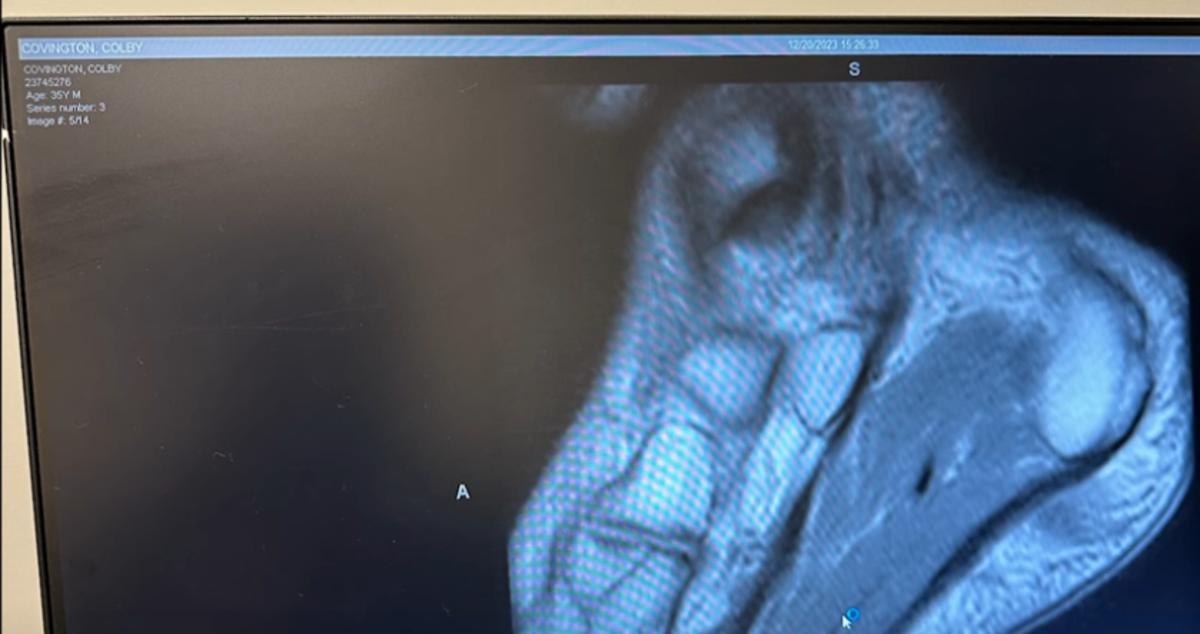

Covington claimed he broke his foot in the opening frames of his fight with Leon Edwards on December 17, 2023, providing an X-ray image as proof.

Although Burns' take is purely anecdotal, Covington's name can be seen on the x-ray he provided: